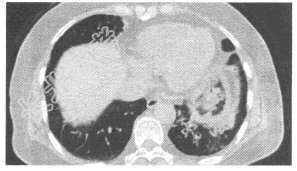

- 单项选择题患者,女, 57岁,咳嗽、咳痰两个月余, 3天前咯鲜血一次,约5ml, 作胸部CT扫描如图。则应诊断为

A、周围型肺癌

B、支气管肺炎

C、中央型肺癌

D、支气管扩张

E、肺泡蛋白沉积症